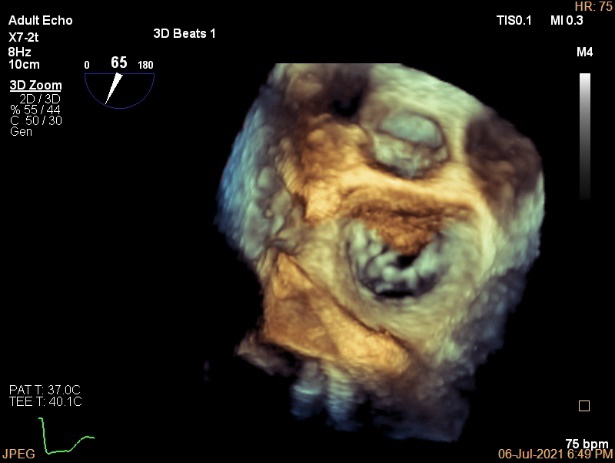

术前超声诊断:

长轴:左室下后壁节异,LAV:101ml,LVEDV:239ml

Bicom:MR(重度),返流束宽15.8mm,返流面积10.6cm²

PISA法定量EROA:0.69cm²,Rvol:168ml,RF:55%

肺静脉血流频谱呈收缩期反向

3D MV View

3D-color MV view:血流主要来源于2区近3区

Qlab软件勾画估测瓣口面积约:6.16cm²

二尖瓣口平均跨瓣压差:1mmHg

TEE Bicom返流量评估

TEE 4-Ch view返流量评估